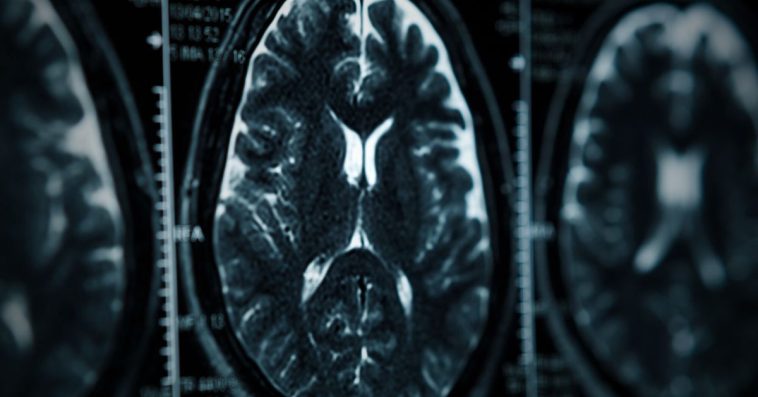

Zespół badawczy postawił sobie ambitne zadanie – wykorzystując nowoczesną aparaturę medyczną, postanowił dokładnie przyjrzeć się temu, co dzieje się w głowach osób po zakażeniu. Porównano je z grupą kontrolną ludzi, którzy nigdy nie zetknęli się z wirusem.

Eksperci z Griffith University zastosowali zaawansowaną metodę obrazowania medycznego, aby zbadać stan neurologiczny pacjentów. Dr Kiran Thapaliya, główny autor publikacji w czasopiśmie naukowym poświęconym badaniom mózgu i odporności, przekazał istotne informacje na temat przeprowadzonego eksperymentu.

Specjaliści skoncentrowali się na fragmentach mózgu odpowiedzialnych za zapamiętywanie, myślenie oraz ogólną kondycję układu nerwowego. Przeanalizowali zarówno istotę szarą, jak i białą. Różnice między grupami uczestników były wyraźnie widoczne we wszystkich przypadkach.

Zastosowana metoda pozwoliła wykryć modyfikacje w substancjach chemicznych odpowiedzialnych za przekazywanie impulsów nerwowych. Zaobserwowano także zmiany w natężeniu sygnałów oraz budowie tkanek mózgowych.